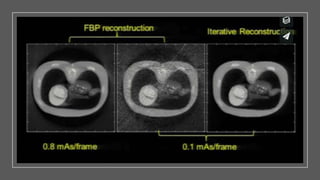

ADAPTIVE ITERATIVE STATISTICAL RECONSTRUCTION Thereare a large variety of algorithms used, but each starts with an assumed image, computes projections from the image, compares it with the original projection data, and updates the image on the basis of the difference between the calculated and the actual projections. These are called adaptive statistical iterative reconstruction algorithms. This new advanced reconstruction technique can reduce image noise, thereby improving image quality by improving low-contrast detectability. Compared with standard filtered back-projection methods, this technique has been shown to reduce the radiation dose to the patient by as much as 50%.

Most IRT resultsin changes in image appearance compared to FBP. Most IRT come in different strengths of noise reduction potential. Initial implementation IRT should generally start at low strength. IRT do not reduce dose by itself but rather allow user to reduce dose compared to FBP.

Guess what theimage slice should be ( uses FBP) Compute the projection data. Forward project the guess for comparison of the guess projection data with the acquired projection data. Calculate the ratio between the guess projection data and the measured projection data ( this is a measure of error in guess). Do a weighted back projection of these ratio. Multiply the guess image by the back projected ratio (i.e. Corrections) to get the updated image. Begin the cycle al over again with the updated image as the new guess.